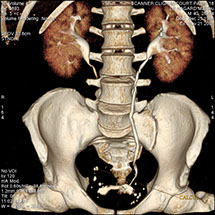

Le scanner comporte un lit d'examen, sur lequel le patient est allongé, qui va se déplacer lentement pendant l’examen et un anneau qui va tourner autour du patient en émettant des rayons X (il contient le tube à rayons X et les récepteurs). Les rayons X vont traverser la région à étudier et permettre d’obtenir des images en coupe de la zone à étudier. Des traitements de numérisation informatique permettront d'obtenir  des images 2D ou 3D dans différents plans et volumes.

Grâce aux scanners multidétecteurs (ou multi-barrettes) à acquisition spiralée, on obtient une exploration très précise d'un large volume du corps humain pour un temps d'acquisition de quelques dizaines de secondes.

C’est un élément majeur dans la panoplie radiologique. L’apport diagnostique du scanner est important notamment dans :

• Les pathologies abdominales : foie, reins, pancréas, (calculs, kystes, tumeurs, …).

• Les suivis en cancérologie.

• Les pelvimétries.

• Les pathologies vasculaires (dilatations d’artères : anévrysmes, les rétrécissements : sténoses).